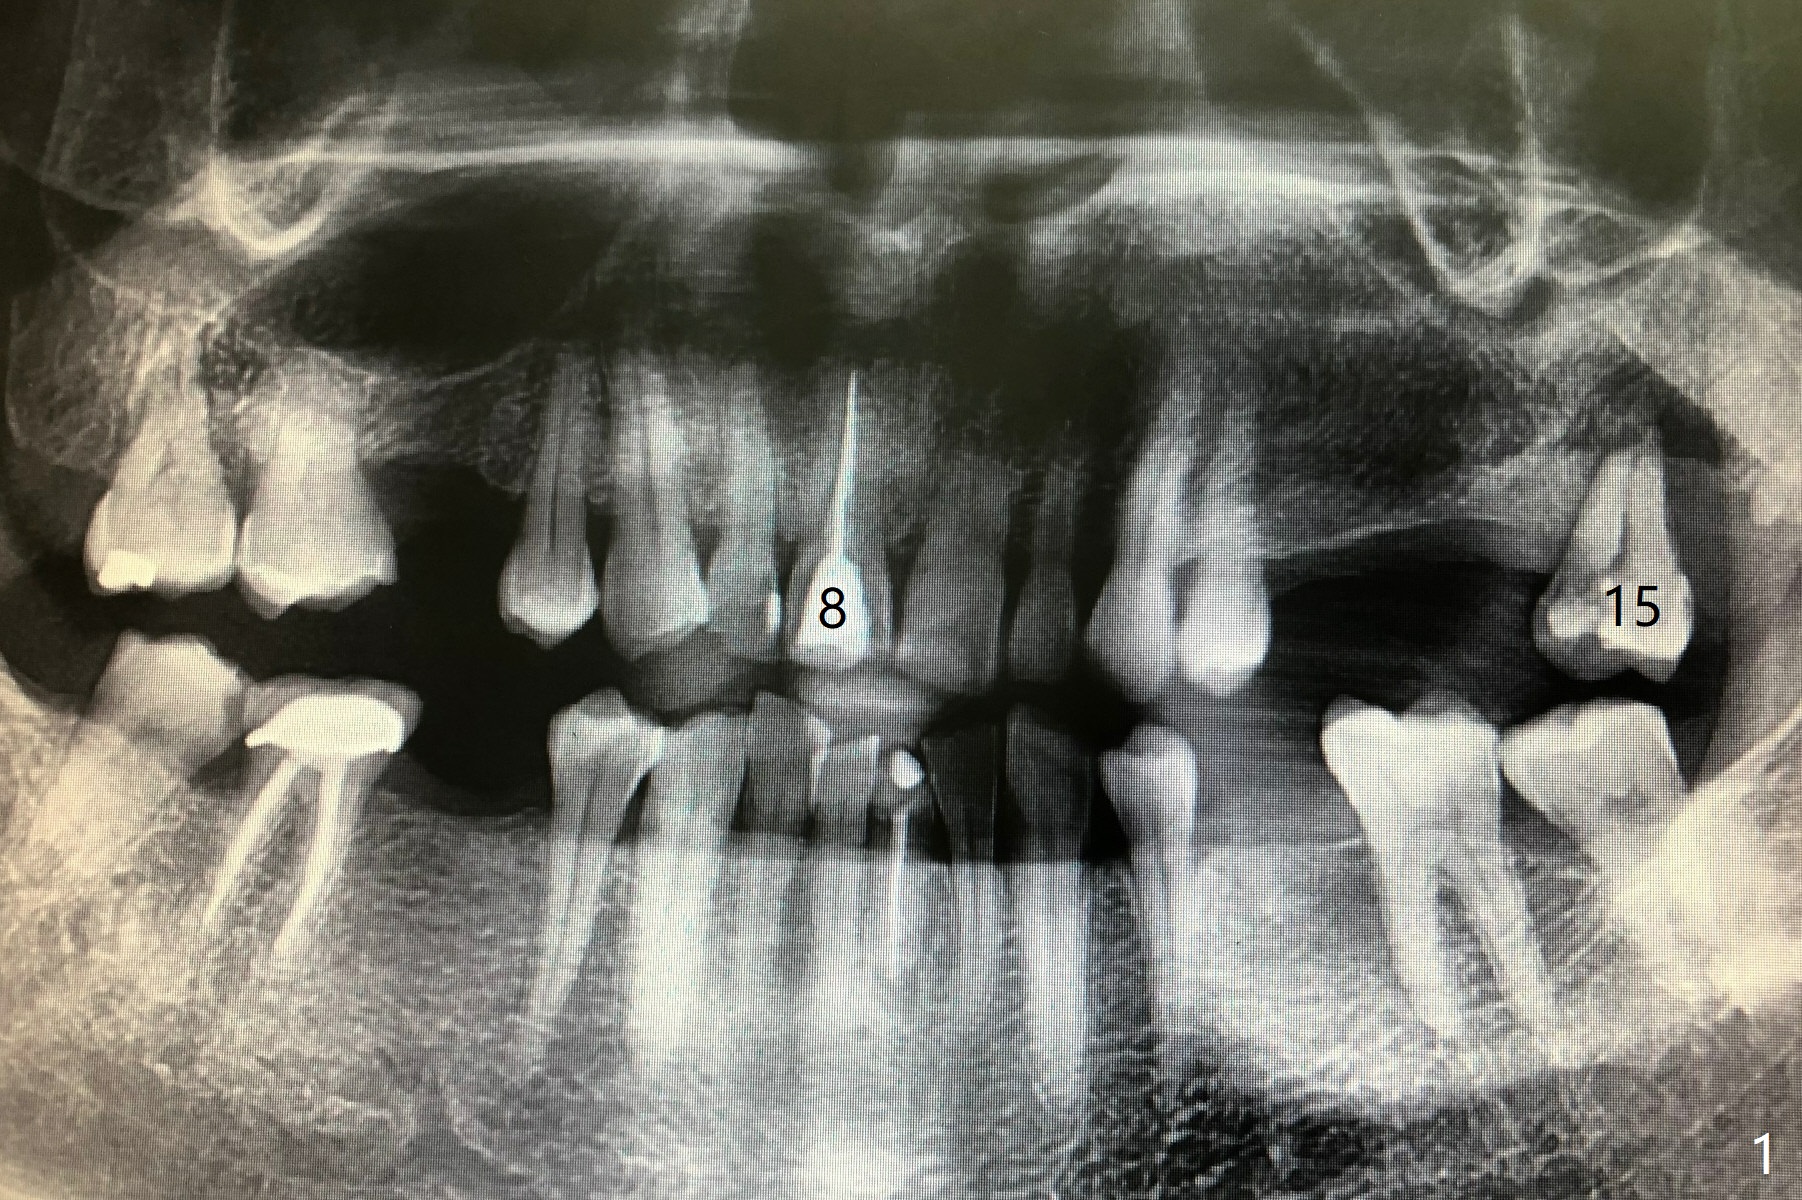

A 55-year-old man have several missing teeth with #8 crown subgingival fracture and #15 mobility (Fig.1,2). It suggests heavy occlusion. A long implant is expected. If osteotomy remains palatal, place an IBS implant (3.5 or 4.0x13 mm). Also prepare UF for cosmetics and longer implant. The bone at #15 should be low, a good indication for IBS implant at the later stage.